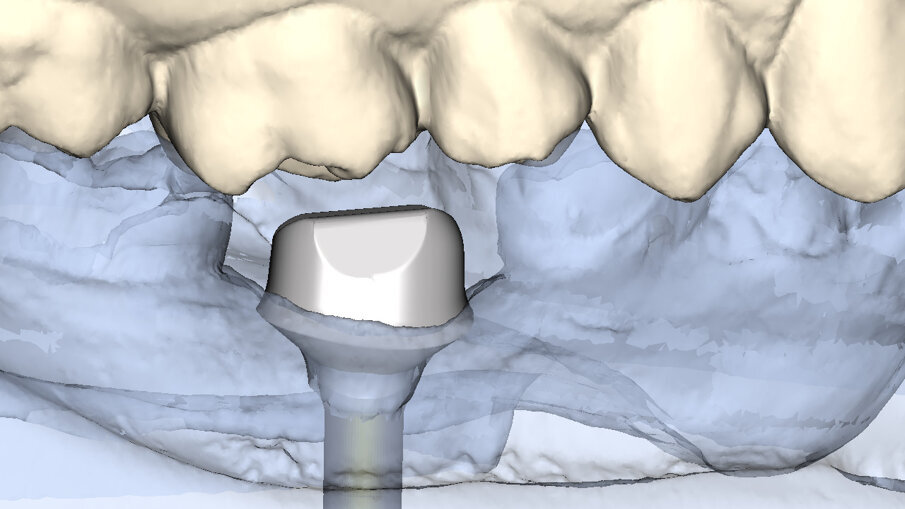

Fig. 6: Using a surgical stent, the osteotomy could be performed in an adequate position in 3D, using the zenith of the cervical contour of the planned restoration as a reference point.

Fig. 7: The implant was placed 3 mm apical to the cervical contour of the planned restoration, symmetrically from

the mesial to distal aspect, and 2 mm to the lingual aspect in order to preserve the buccal bone that would support the soft tissue.